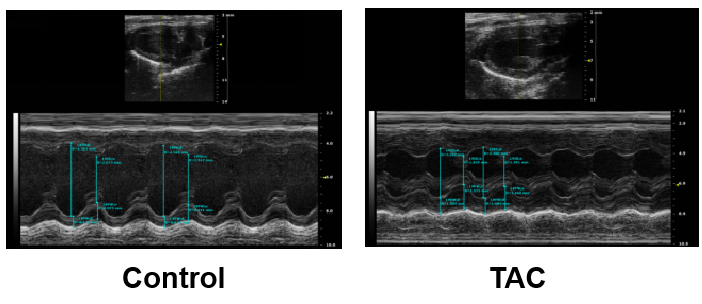

模型验证:术后8周进行心脏超声检测:结果表明与对照组相比,模型组左心室在舒张期或收缩期的直径明显缩小